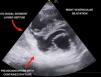

A 62-year-old woman with no personal history of disease was seen due to epigastric pain lasting four days, suffering a right-side pure hemi-motor lacunar stroke with anodyne multimodal CT findings. The ECG tracing evidenced inferior ST-segment elevation with Q waves, and the patient was admitted to intensive care. Transthoracic echocardiography showed septal-basal interventricular communication (IVC) presenting an akinetic inferior aspect with thinning and hyperechogenicity suggestive of pseudoaneurysm with possible contained myocardial rupture (Fig. 1, Video 1). Emergent surgery was discarded due to the neurological condition of the patient and surgical risk due to friability of the tissues. While in wait for the final decision, a cardiac MRI was performed (Fig. 2), after which the patient suffered cardiac arrest with pulseless electrical activity secondary to tamponade, with futile resuscitation efforts (Fig. 3, Videos 2 and 3). Mechanical complications following acute myocardial infarction, while unusual nowadays, remain a potentially fatal and time-dependent disorder in which imaging techniques such as echocardiography continue to play a key role.